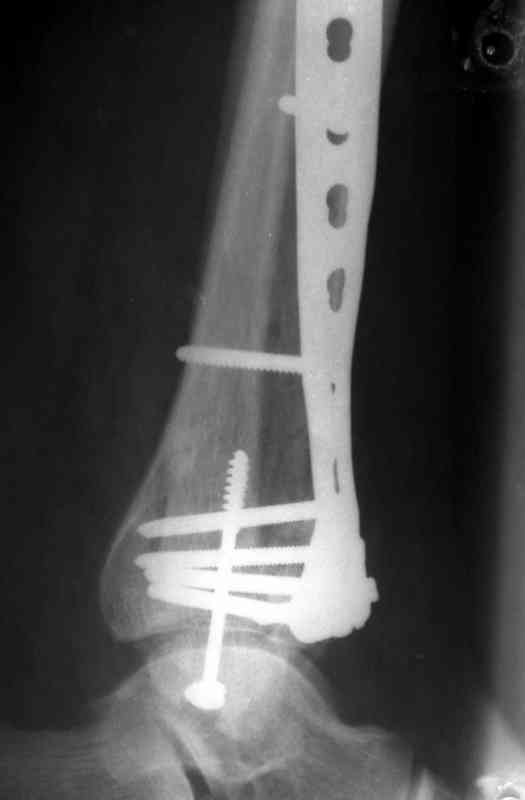

Послала ещё два снимка, если не пройдут, пошлю ещё. Дрягин. Если есть вопросы, готов ответить.

Посылаю результат лечения предыдущего больного через год.